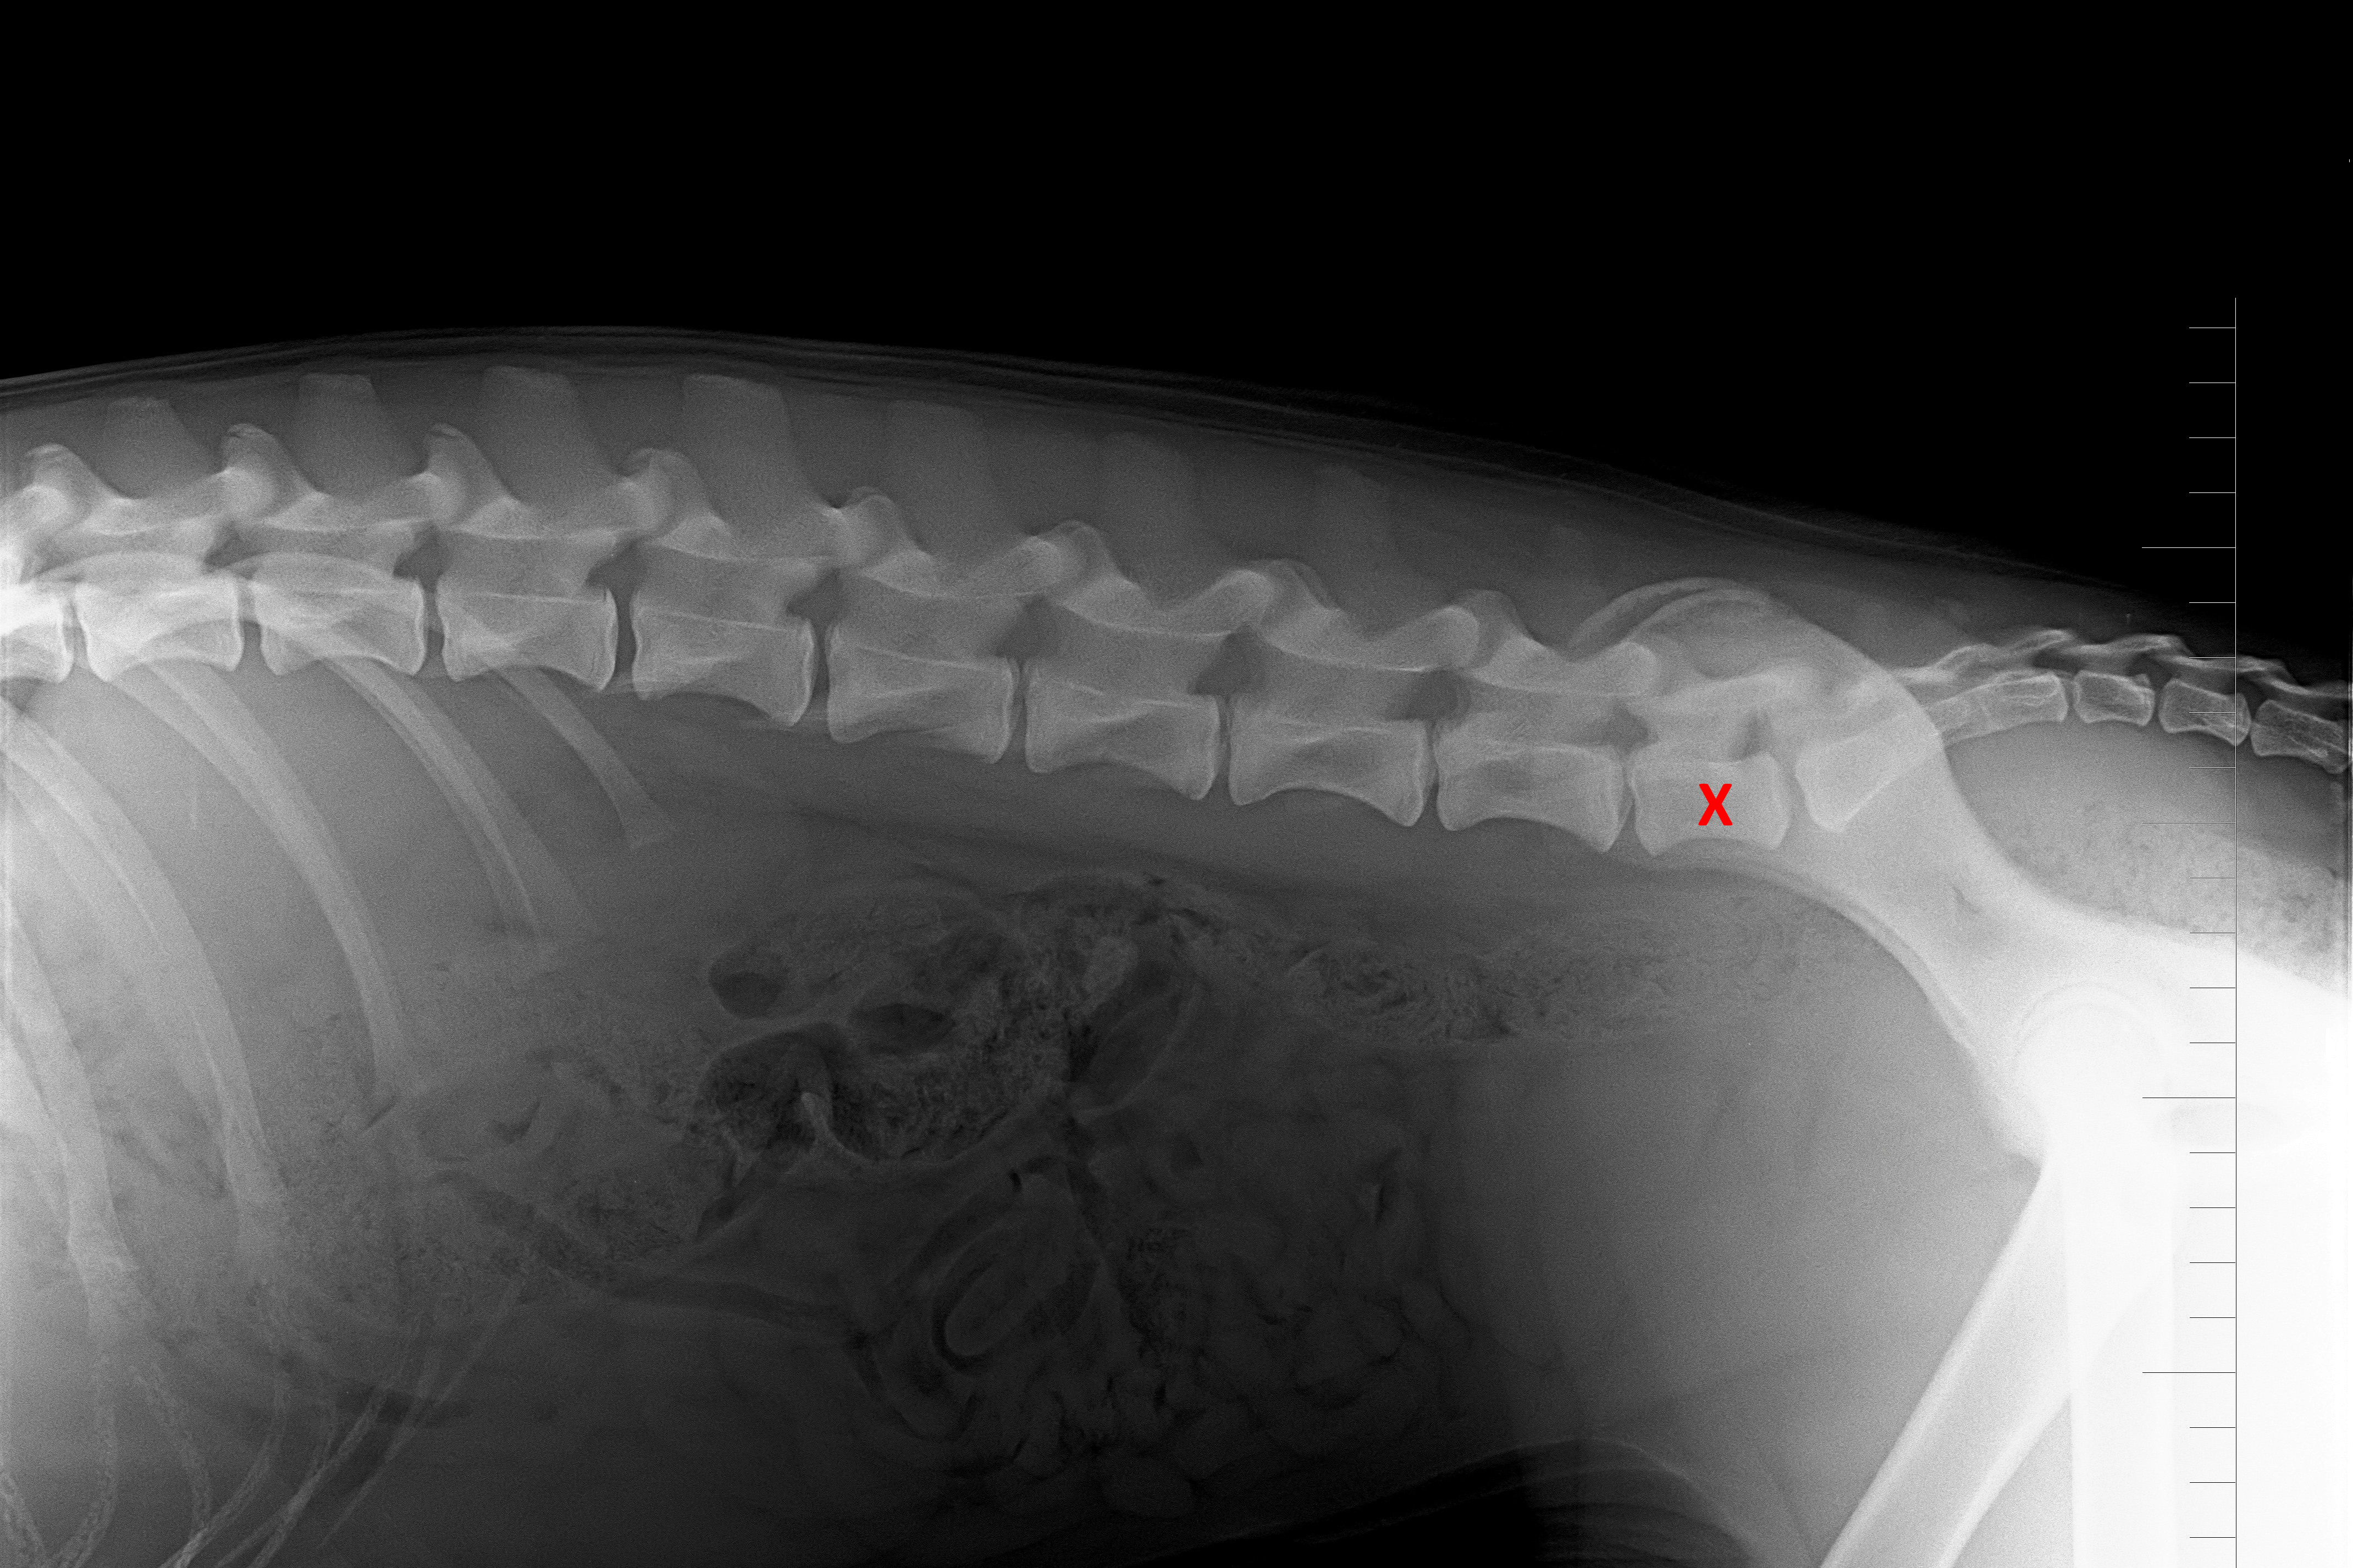

(5) 7 měsíců lat

(5) typ 3 páteř VD